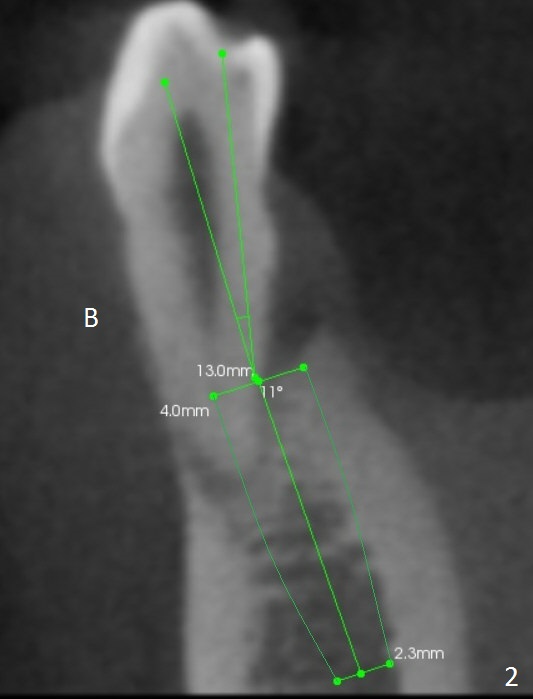

A 44-year-old man will return for #28 extraction and immediate implant 2-3 months after removal of the implant at #31 (Fig.1). After Clindamycin treatment, start osteotomy in the middle of the lingual wall of the socket (Fig.2,3 red line) with 1.6 mm for 13 mm (from oblique to straight). Take PA to determine clearance from the Mental Loop (Fig.1 red dashed line). If the trajectory is right, use 3.3 mm Magic Drill (MD) and possibly 3.8 mm one for short distance, since the bone density near the socket 700 units, while apically 100 units. Or use a 4x11 mm IBS dummy implant instead of 3.8 mm MD. An angled abutment may be used (Fig.2). Also prepare UF in case the gingiva is thick.